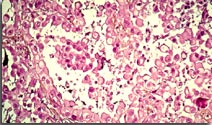

Au total 209 patients ont été inclus. L’âge médian est de 69 ans et 81,8 % sont des hommes. Les histologies sont les suivantes : épithélioïde (48 %), sarcomatoïde (12,6 %), mixte (5,2 %), et non spécifié (34,2 %). La proportion de malades traités par chimiothérapie entre 1998 et 2005 est de 29,3 % par rapport aux 60,2 % de patients traités entre 2006 et 2011. La médiane de survie sur la période 1998-2005 est de 8,2 mois (intervalle de 3,7 à 19,3 mois). Sur la période de 2006 à 2011, la survie médiane globale est de 9,8 mois (de 3,7 à 15,8 mois) avec pour les patients ayant reçu une chimiothérapie par carboplatine-pemetrexed, une médiane de survie de 12,7 mois (de 9,8 à 22,7 mois), différence non significative.